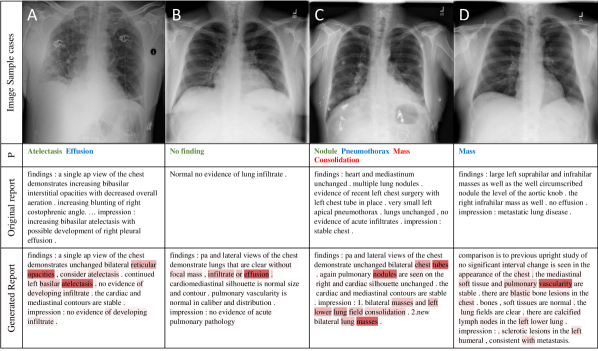

Refer to caption

Figure 4: 4 sample image Classification Predictions (P) along with original and generated reports. Text attentions are highlighted over the generated text. Correct predication is marked in green, false prediction in red and missing prediction in blue.

Figure 10 illustrates 4 sample results from the proposed automatic classification and reporting system. Please see more examples in the appendix A. Original images are shown along with the classification predications, original reports and generated reports. Text-attended words are also highlighted over the generated reports. If looking at generated reports alone, we find that they all read well. However, the described diseases may not truly appear in the images. For example, ‘Atelectasis’ is correctly recognized in sample A but ‘Effusion’ is missed. ‘Effusion’ (not too far from the negation word ‘without’) is erroneously highlighted in sample B but the system is still able to correctly classify the image as ‘No finding’. In sample D, the generated report misses ‘Mass’ while it states right about the metastasis in the lung. One promising finding is that the false predictions (‘Mass’ and ‘Consolidation’) in sample C can actually be observed in the image (verified by a radiologist) but somehow did not noted in the original report, which indicates our proposed netowrk can in some extent associate the image appearance with the text description.